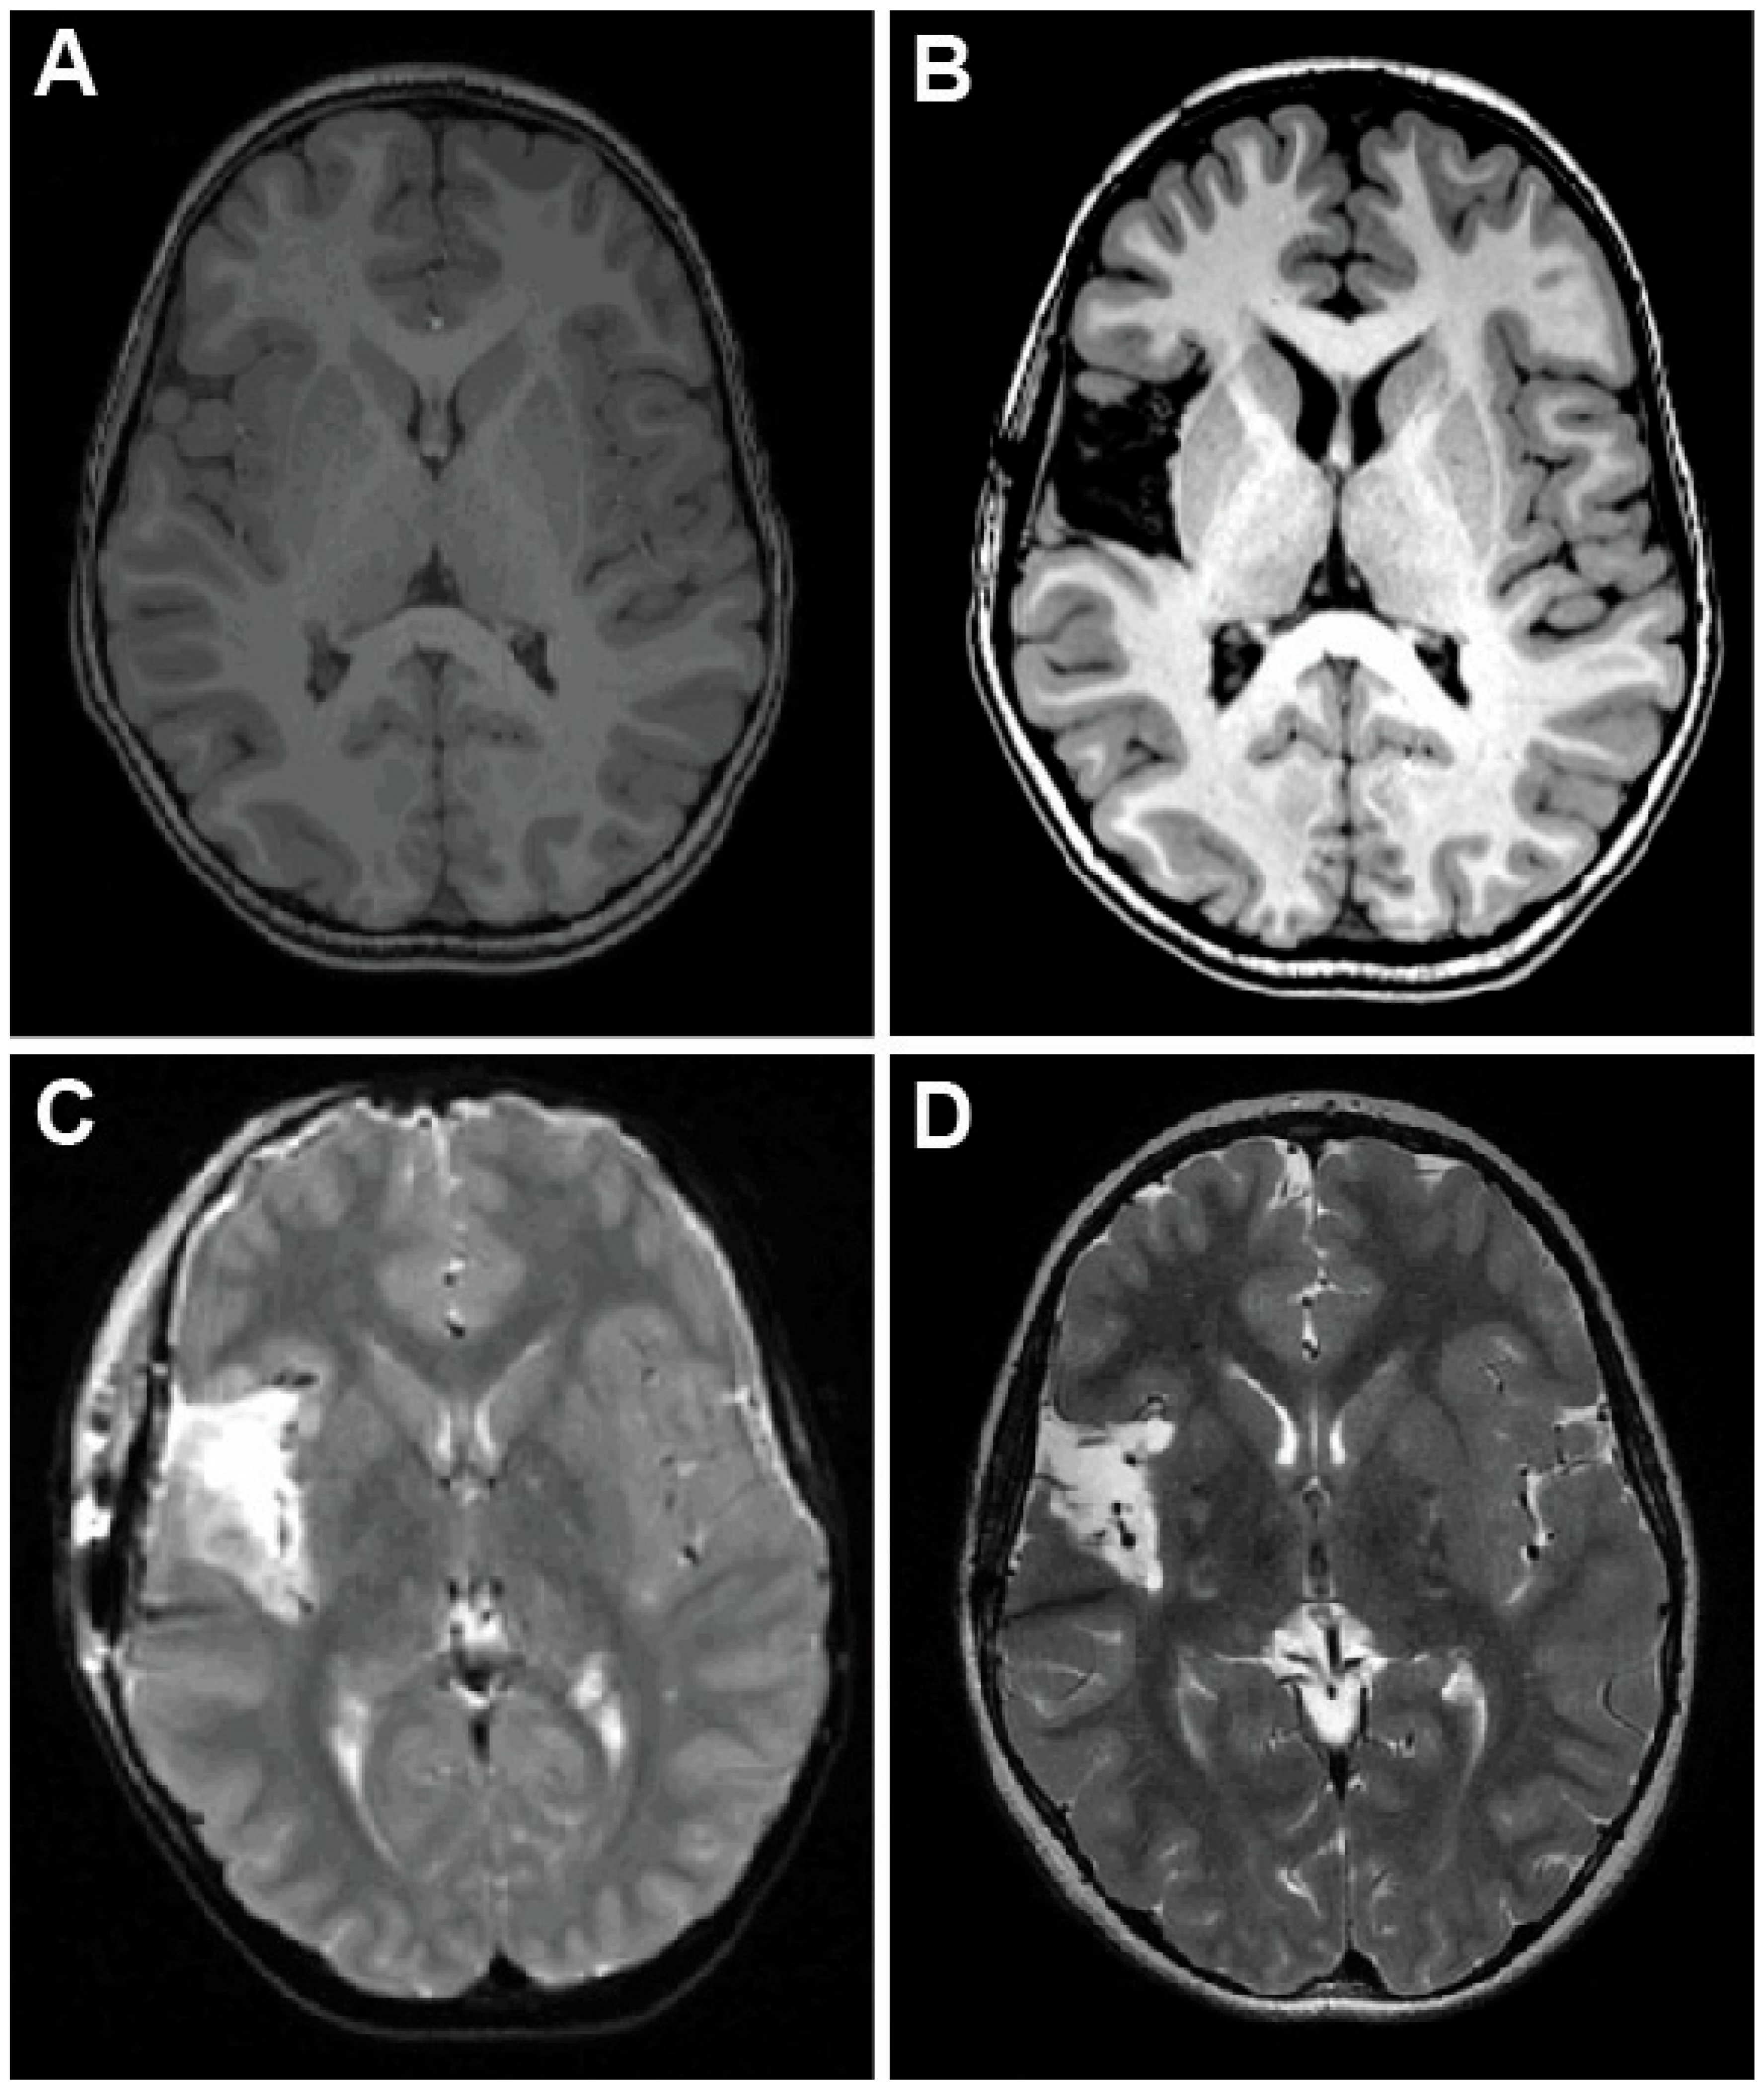

2.1. Case 1—Trans-Sylvian Approach for Insular Focal Cortical Dysplasia

2.2. Case 2—Trans-Opercular Resection for Focal Cortical Dysplasia in the Left Superior Temporal Gyrus and Posterior Insula

2.3. Case 3—Trans-Opercular Approach for Infarct Spanning Left Posterior Insula and Parietal Lobe

2.4. Case 4—Trans-Sylvian Approach for Idiopathic Insular Epilepsy